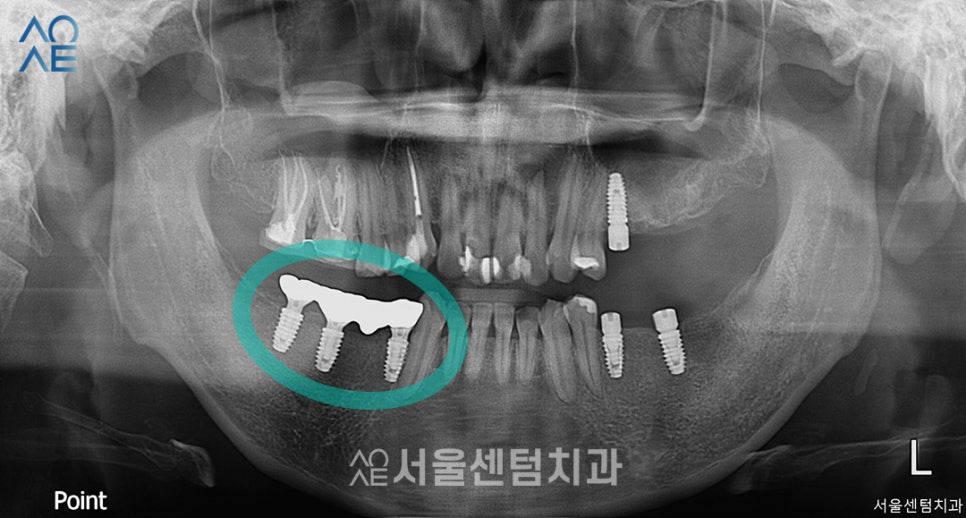

위 이미지는 구강검진을 위해 첫 내원했을 때

촬영한 엑스레이 사진입니다.

다른곳에서 치료를 받은 치아도 보이고

어금니를 상실한 부분도 보였습니다.

전체적으로 치료할 부분이 많이 보여서

상세 내용은 아래 표에서 설명드리겠습니다.

(엑스레이에선 왼/오가 반대로 나옵니다)

| 🦷현재 상태 &치료 계획🦷 |

|---|

| (1) 현재 상태🔹 오른쪽 아래 어금니는 아예 없음🔹 왼쪽 아래 사랑니는 깨져서 치아 기능을 할 수 없음🔹전체적으로 잇몸이 내려가있음 |

| (2) 치료 계획🔹왼쪽 사랑니 발치🔹왼쪽 위 / 오른쪽 아래 어금니 임플란트 식립 |